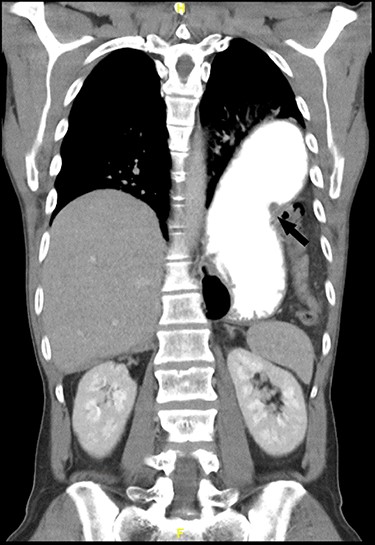

For primary diagnosis, computed tomography (CT) scan is most accurate when suspecting a diaphragmatic lesion [1]. Lesions without herniation are difficult to detect even in thin slices with multiplanar reconstruction. Possible direct signs, besides discontinuity, are the ‘dangling diaphragm sign’, showing a rolled up free diaphragmatic border. Indirect signs are the ‘collar sign’, organs are constricted when passing through the defect (Fig. 1), or the ‘dependent viscera sign’, where abdominal organs touch directly the thoracal wall without interposition of the lung in the supine patient [1, 3] (Fig. 2).

A 47-year-old male patient consulted our emergency department with acute epigastric pain without dyspnea or alteration of bowel function. A thoracic X-ray showed a dilated stomach intrathoracally and colon parts. A CT scan confirmed a left-sided diaphragmatic hernia (69 × 45 mm) with an upside down stomach, herniating small bowel and colon (Figs 1 and 2). The patients’ history includes a severe motor vehicle accident 20 years ago with following coma during 3 months but without abdominal surgery, suggesting a traumatic origin of the hernia.